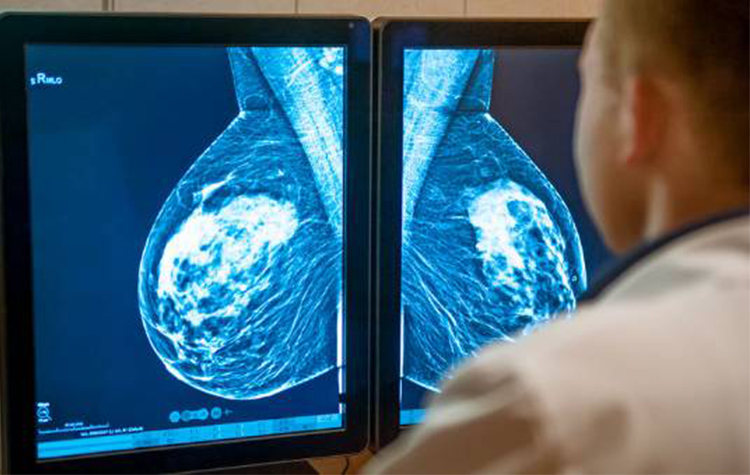

Kanserli Meme Nasıl Fark Edilir?

Meme kanseri, meme dokusunda yer alan ve süt kanalını oluşturan hücreler ile süt yapıcı hücrelerin kontrolsüz çoğalması sonucu oluşur. Kadınlarda görülen kanser türlerinin yaklaşık %33’lük bölümünü oluşturan meme kanserinde erken teşhis tedavinin başarısını artırır.